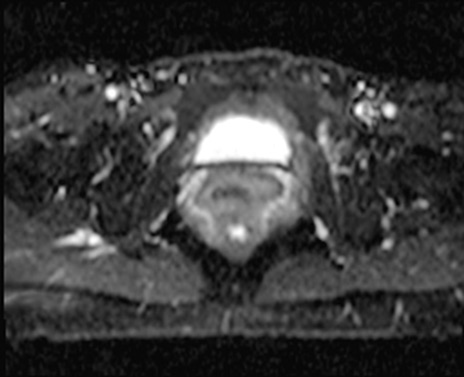

【症例】40歳代女性

【主訴】上下腹部痛

【現病歴】2日目から下腹部痛あり。夜間は痛みで眠れなかった。昨日より上腹部痛と下痢が出現。臥位で痛みは軽快したため、休んでいた。本日になって臥位でも立位でも痛みが強くなってきたため救急要請。

【既往歴】子宮内膜症

【身体所見】部:平坦・軟、左上下腹部に圧痛あり、反跳痛あり。

【データ】WBC 21800、CRP 26.78

MRI(4日後)